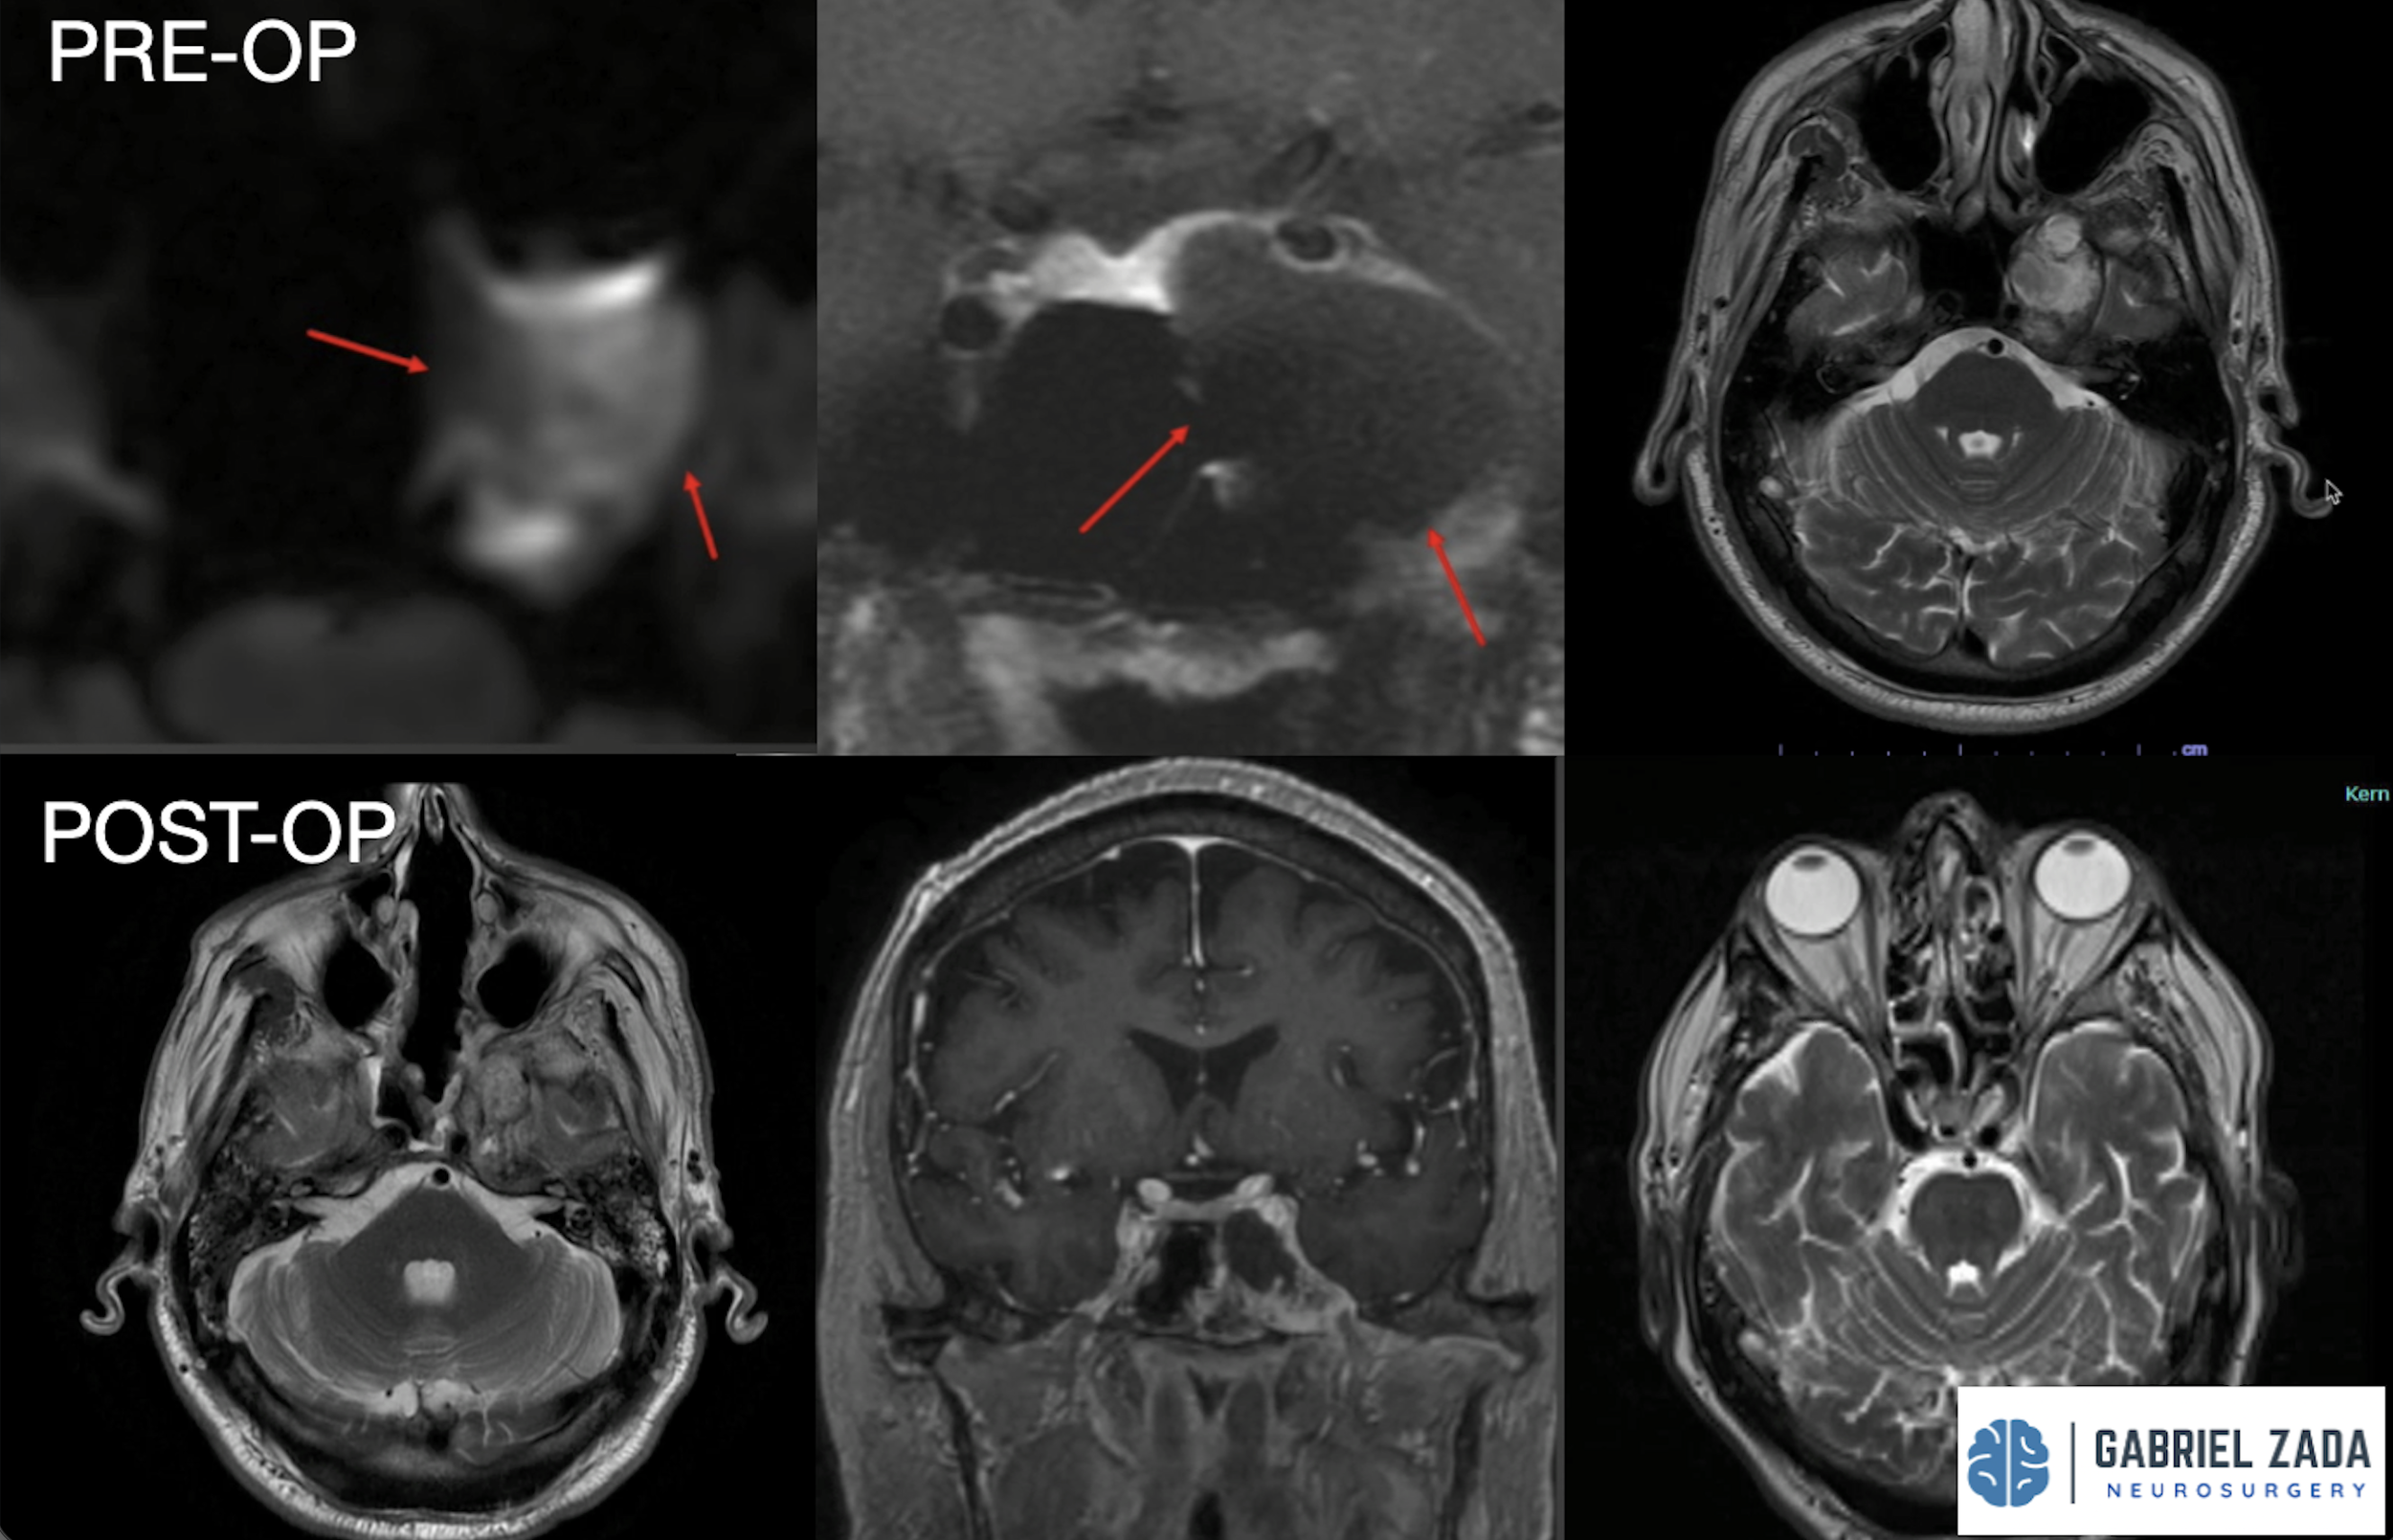

Explore this comprehensive gallery featuring pre‑ and post‑operative imaging of patients with skull‑base tumors treated by Gabriel Zada, MD, MS, FAANS, FACS. These cases highlight Dr. Zada’s expertise in advanced neurosurgical techniques and outcomes.

*Representative cases shown for educational purposes. All images de-identified. Individual results vary.